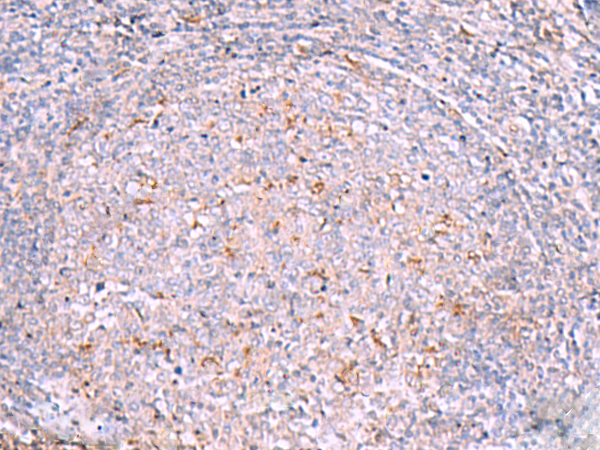

IHC positive control:

Human tonsil

IHC Recommend dilution:

20-100